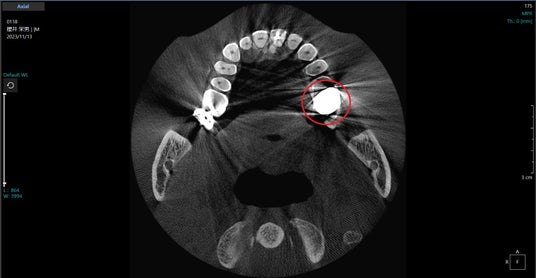

PanoACT 3D Upgradeシリーズは、パノラマやセファロの高画像品質だけでなく、CBCTの課題解決にも取り組んでおり、【図6ー2】に示したように、金属アーチファクト低減機能を開発しています。

アクシオン・ジャパンのアルゴリズムは、金属によって 生じた投影データ上の誤差を補正することで金属アーチファクトを低減する方法で、アーチファクトの発生要因によらずに投影データの補正を行うため、金属部が連続してフォトン不足が深刻な状態においても効果的に影響を低減できていると高評価を受けています。

【図6ー1】:PanoACT 3D Upgradeの金属アーチファクト低減機能例

【図6ー2】:PanoACT 3D Upgradeの金属アーチファクト低減機能例